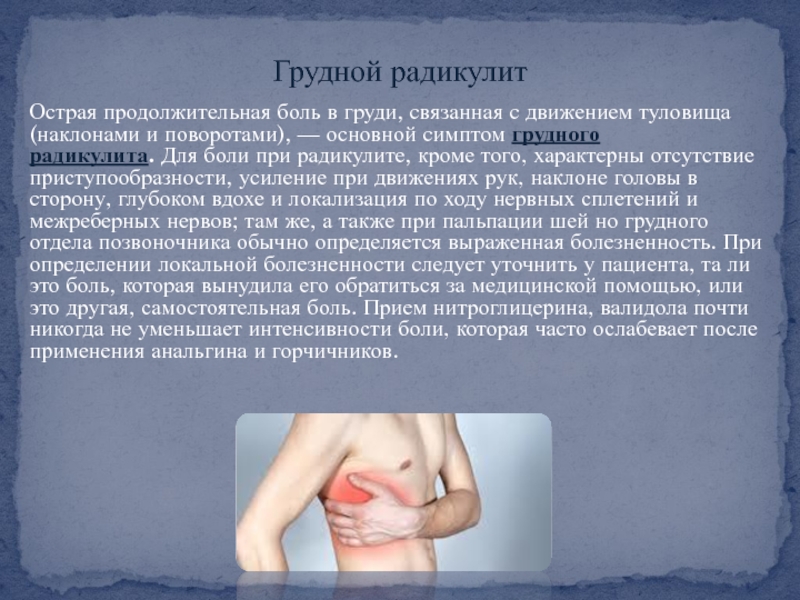

Причины и лечение боли в грудной клетке при кашле